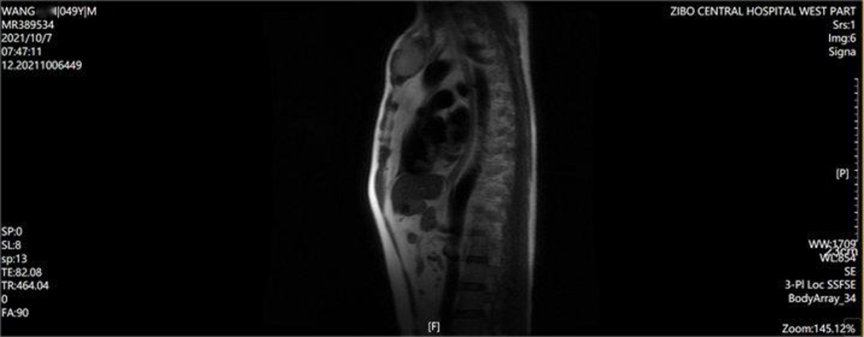

患者男性,49岁。因“发现胸骨肿物2月”于2021年10月入院。患者自诉伴有胸部疼痛。当地医院查胸骨MRI提示胸骨柄区占位、左侧约第4、5后肋水平占位及部分胸椎多发异常病灶。

胸骨MR:胸骨柄区占位,左侧约第4、5后肋占位,多发胸椎多发异常病灶。